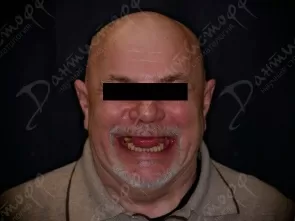

Фото работ